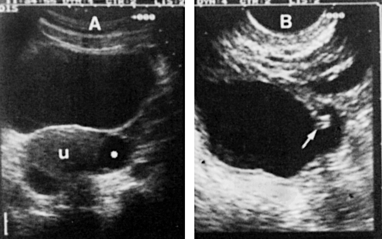

Fig. 8-13 - Hidrossalpinge (via suprapúbica):

a) Diagnóstico inicial de cisto ovariano estável ao longo de várias ecografias sucessivas.

b) Em via vaginal, aspecto de plicatura (®) característica de uma hidrossalpinge.